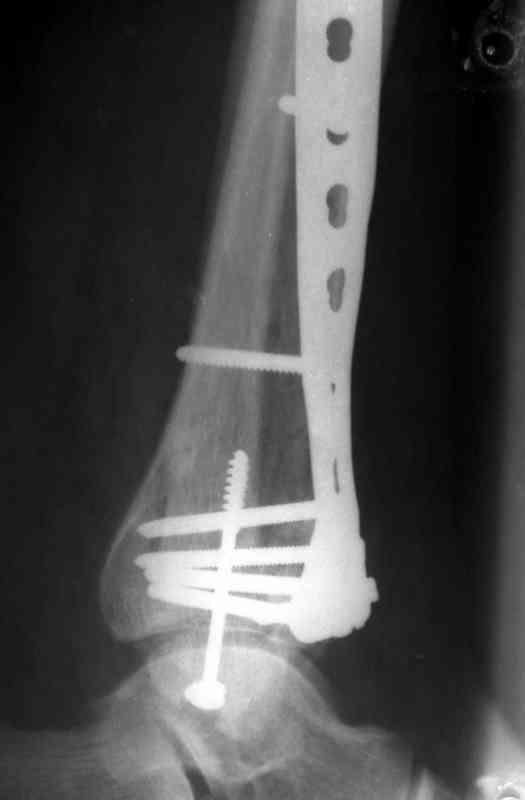

На рентгенограммах типичный перелом пилона по типу С-3. есть опыт до 100 открытых опреаций у нас в клинике. 20 примерно в год. Принцип один -все внутрисуставные переломы нуждаются в открытой репозиции и внутренней стабильной фиксации. При поступлении КТ не надо, так как получается только нагромождение костей. Истинной картины нет. Главное восстановить длину малоберцовой кости - это ключ к успеху. При поступлении меньше всего надо думать о сосудистых расстройствах, т.к. сама операция и репозиция даже сначала частичная даёт улучшение сосудитых нарушений. Причём очень быстро. Операция в 2этапа. При поступлении доступ позади наружной лодыжки, причём обязательно. После этого репозиция малоберцовой кости и фиксация пластиной 1/3 трубки под винт 3,5. Дренаж и любой аппарат наружной фиксации. Затем после спадения отёка на 5-7-10 день аппрат снимается и дугообразный разрез спереди от медиальной лодыжки 10-12 см. Главной чтобы расстояние между 1 и вторым разрезом было не меньше 7-8 см. Тогда не будет некрозов лоскутов. Таранная кость используется как матрица на неё укладываются отломки и фиксируются пицами. Ренг-контроль. Отломки лежат все отдельно, но ничего не высыпется. При переломах С-3 всегда нужна костная пластика (из крыла). Фиксация пластиной лист клевера простой или LCP. Гипс не нужен. Дренаж до 48 часов. Операция длится 3-4 часа обязательно без жгута. Посылаю примерно такой же случай.

Послала ещё два снимка, если не пройдут, пошлю ещё. Дрягин. Если есть вопросы, готов ответить.